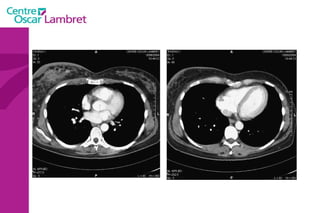

Le médiastin C'est l’espace au centre du thorax. Il est situé en avant de la colonne vertébrale et peut être divisé en plusieurs quadrants.  Il est divisé, par convention, en : médiastin postérieur :  contenant notamment  l’oesophage et l’aorte descendante.  médiastin moyen :  contenant les voies aériennes supérieures : trachée et sa division (carène).  médiastin antérieur :  contenant le cœur, l’aorte ascendante, les artères pulmonaires et la veine cave supérieure.

Le médiastin Le médiastin   antérieur  comprend : L’aorte ascendante Le tronc pulmonaire La veine cave supérieure Les cavités cardiaques sauf l’atrium gauche La loge thymique

Le médiastin Le  médiastin moyen  comprend : La trachée La carène Les pédicules pulmonaires : Les bronches souches Les veines et les artères pulmonaires Le segment horizontal de la crosse de l’aorte Le Tronc Artériel Brachio-Céphalique L’artère carotide primitive gauche La crosse de la grande veine azygos

Le médiastin Le médiastin  postérieur  comprend : Le canal thoracique La grande veine azygos et les veines hémi azygos L’œsophage L’aorte descendante et ses branches